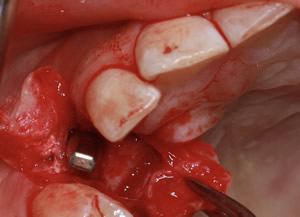

症例1

- 年齢・性別

- 55歳女性

- 治療期間

- 2ヶ月

- 抜歯

- なし

- 治療費

- 66万円

- 備考

- 右下6.7欠損

- 治療内容

- 右下6.7欠損部にインプラント埋入

- 施術の副作用(リスク)

- オペによる知覚障害。インプラントによる歯肉炎。インプラント脱落。